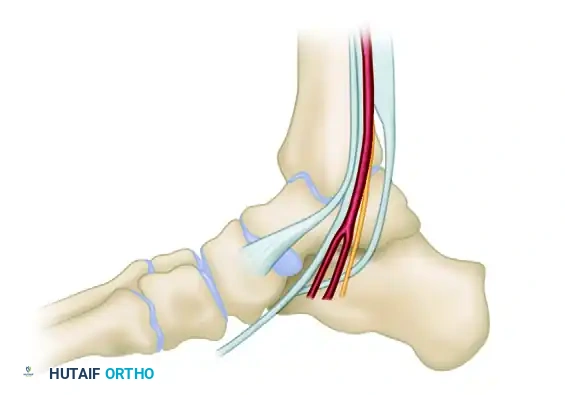

Figure A: Placement of calcaneal and talar screws to avoid the neurovascular bundle and subtalar joint.

3. Talar Screw Insertion

The talar screw is the keystone of the construct. Its placement dictates the alignment of the fixator template.

1. Starting Point: Locate the starting point on the distal medial neck of the talus using fluoroscopy.

2. Trajectory (AP View): Advance the screw parallel to the dome of the talus. This ensures the fixator hinge will align with the ankle's axis of rotation.

Figure B: The talar screw must be strictly parallel to the talar dome on the anteroposterior fluoroscopic view. Dashed lines indicate inaccurate, non-parallel screw placement.

3. Trajectory (Axial View): The screw must be driven roughly perpendicular to the long axis of the foot.

Figure C: The screw is placed perpendicular to the long axis of the foot. Ensure bicortical purchase; two threads should protrude through the far (lateral) cortex of the talus.

4. Calcaneal and Tibial Screw Insertion

- Template Application: Slide the fixator template over the perfectly positioned talar screw.

- Calcaneal Screw: Place the calcaneal screw through the template. By rotating the articulated hinge, this screw can be placed high or low in the calcaneal tuberosity.

> Surgical Warning: A high position in the calcaneal tuberosity is strongly recommended. This position prevents impingement during postoperative dorsiflexion and mitigates the risk of equinus contracture. - Verification: Confirm bicortical purchase of the calcaneal screw on an axial fluoroscopic view of the hindfoot. The center of the fixator hinge should now rest near the middle of the talus.